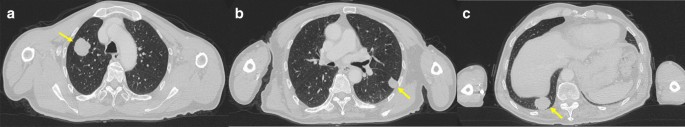

A 76-year-old Japanese man with right oropharynx ACC presented at a general hospital. Computed tomography (CT) detected masses of 23 × 19 mm on the right upper lung lobe, 14 × 12 mm on the right lower lung lobe, and 15 × 14 mm on the left lower lung lobe. 18F-fluorodeoxyglucose positron emission tomography (FDG-PET) revealed abnormal accumulation in the lung tumors. The patient was diagnosed with T3N0M1, stage IVC ACC of the right oropharynx with lung metastases. Despite the lung metastasis, a favorable long-term prognosis was possible after control of the primary tumor. Radical surgery was not indicated for reasons related to functional preservation, and the patient received carbon ion (C-ion) radiotherapy for the primary tumor. The total dose was 64 Gy (relative biological effectiveness) delivered in 16 fractions. After 30 months, there was no recurrence of the primary lesion; however, the metastatic lung tumors had increased in size. The masses had grown to 32 × 30 mm on the right upper lung lobe, 31 × 25 mm on the right lower lung lobe, and 18 × 17 mm on the left lower lung lobe (Fig. 1). The patient consented to sequential treatment with CyberKnife for multiple lung metastases (Table 1). CT images of 1 mm thickness were acquired to plan the treatment. Respiratory migration was assessed by four-dimensional CT. The gross tumor volume (GTV) was delineated based on thin-slice CT images. The clinical target volume (CTV) was identical to the GTV (CTV = GTV). The planning target volume (PTV) included 2 mm margins surrounding the CTV. The organs at risk (OARs; lung, spinal cord, heart, and skin) were outlined on the treatment planning CT scan and dose–volume histogram analysis. D95 was defined as the minimum dose covering 95% of the GTV for the first and the second CyberKnife treatments or the PTV for the third CyberKnife treatment. The dose prescribed for the PTV was used for the third treatment because of its small size. The patient received a total dose of 60 Gy in 10 fractions of D95. The treatment was planned using the MultiPlan System (Accuray). The composite dose distribution is depicted in Fig. 2. The treatment data for the first CyberKnife administration are summarized in Table 2. Conformity and homogeneity indices were calculated according to the following formulas [8]: